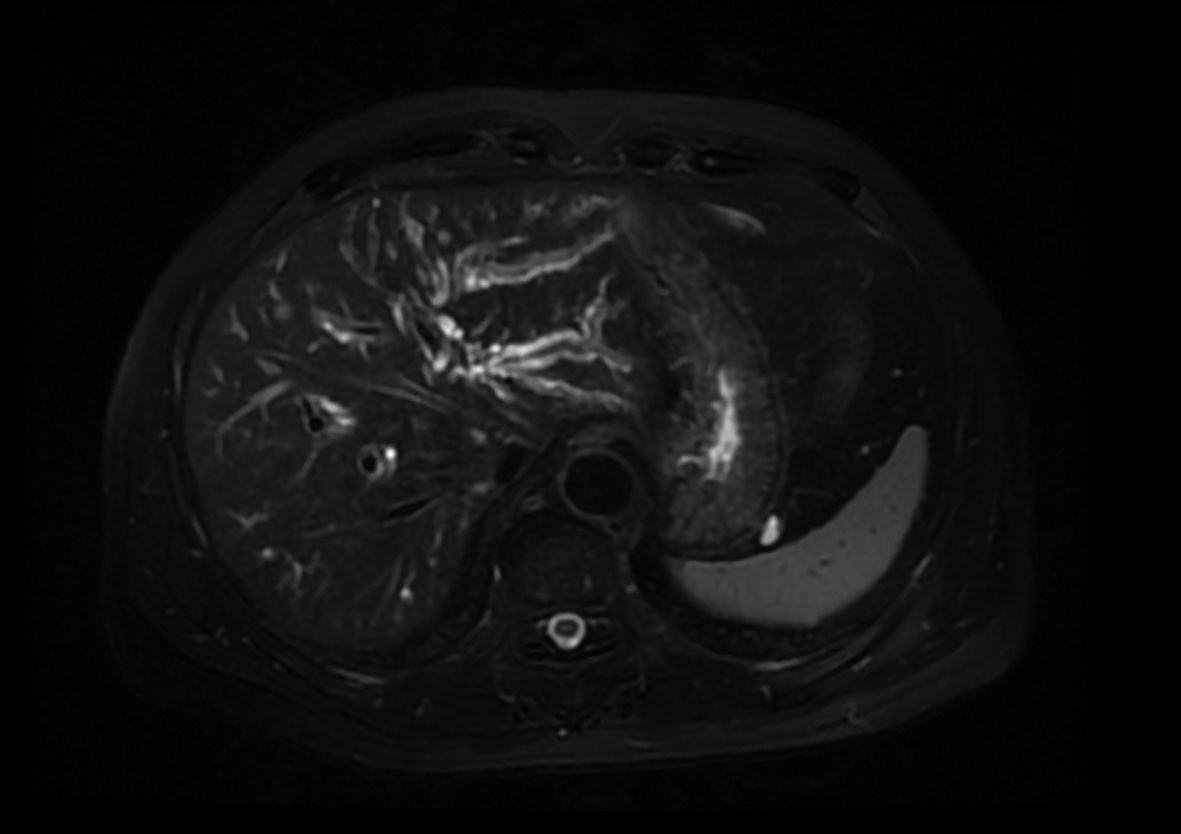

肝移植术后自发性肝破裂出血1例报告

马健, 何力宏, 王凌云, 翟亚楠, 李汛, 张磊

2022, 38(4): 891-893. DOI: 10.3969/j.issn.1001-5256.2022.04.030

摘要(1066) HTML (365) PDF (3041KB)(58)

摘要: